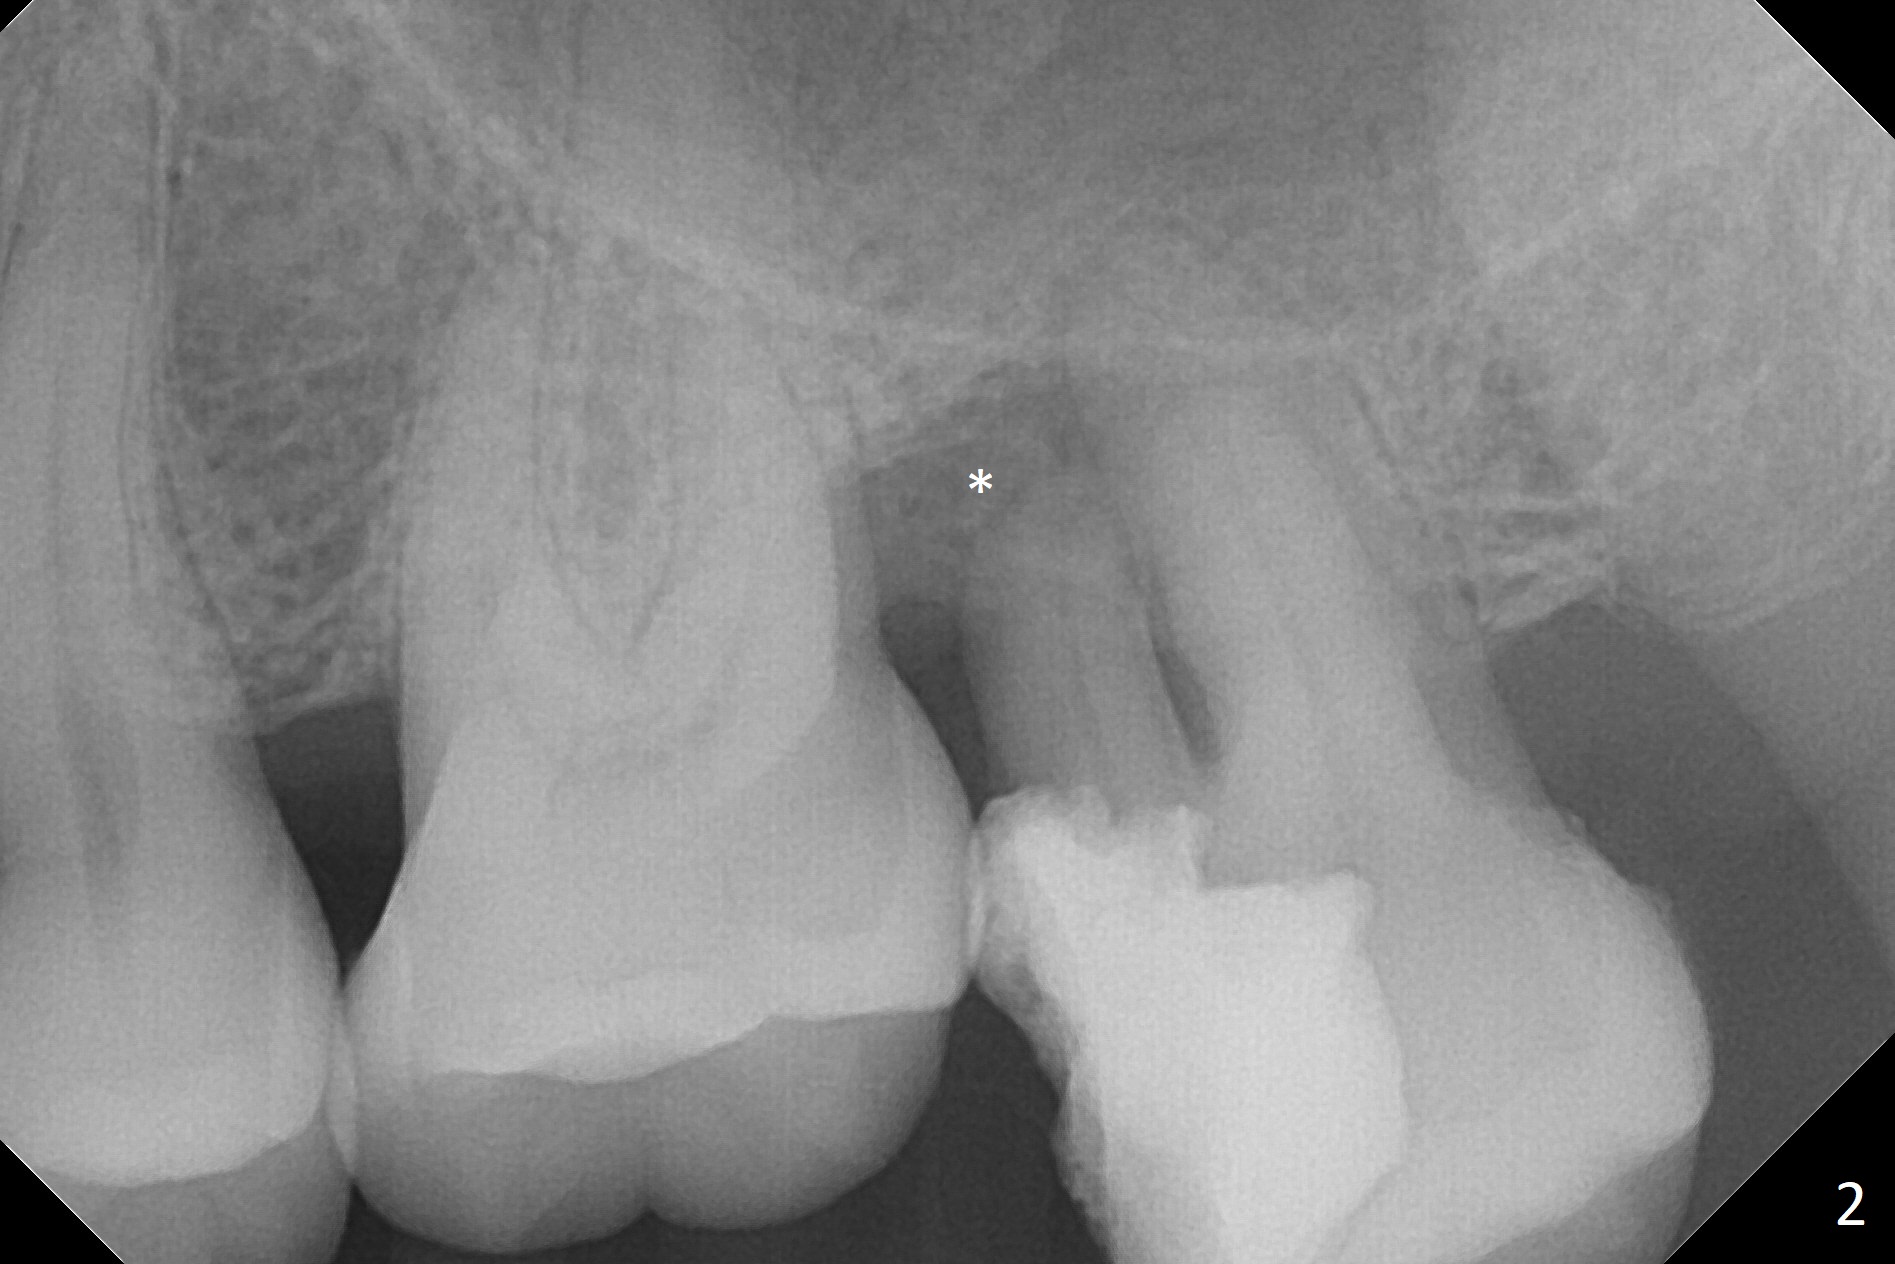

Bone loss seems to be the most severe around the mesiobuccal root (Fig.2 *), from which the osteotomy should stay away (Fig.3). It may be the safest to place an implant in the palatal socket, leaned as buccally as possible so that the coronal end of the implant will be in the center of the extraction socket. Re-measure the palatal socket length from PA and Pan: 8.5 and 10 mm, respectively. The implant length should be around 10 mm. Place bone graft before the final tap and take X-ray.